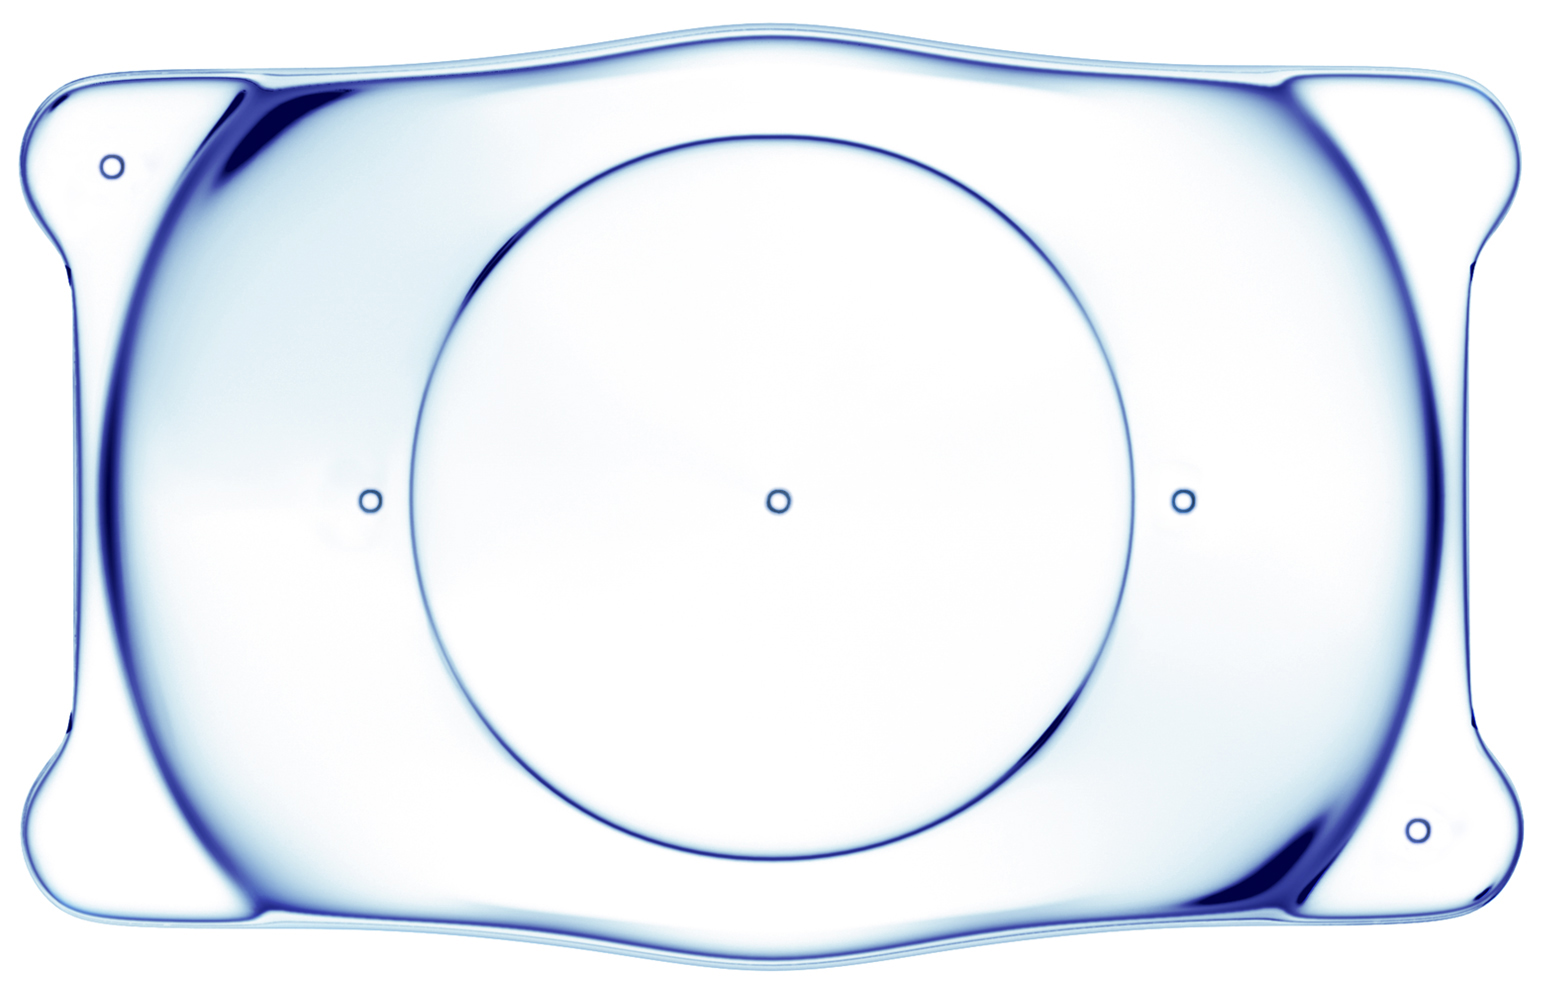

什么是人工晶體植入術(shù)?

ICL人工晶體植入術(shù)是一種做“加法”的手術(shù),通過在眼內(nèi)植入一枚特殊的“隱形眼鏡”,從而矯正近視。安全性高,預(yù)測性好,并且手術(shù)具有可逆性、視覺質(zhì)量高,無需改變角膜形態(tài)等優(yōu)點(diǎn),是一種“可逆”的高清近視手術(shù)方式。手術(shù)后視力提升快,對角膜薄、高度、超高度近視的患者,效果尤為明顯。